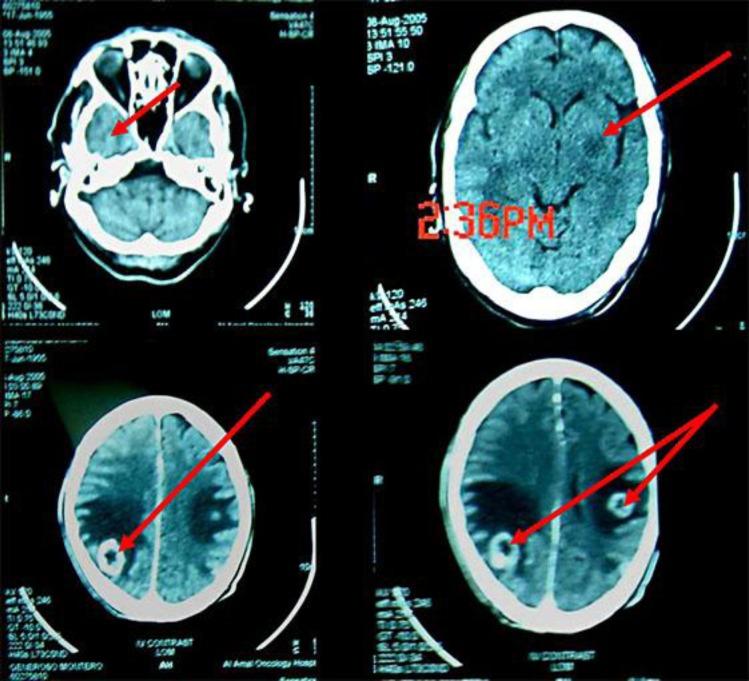

A malignant transformation is known to occur in many nevi such as a sebaceous nevus or a basal cell nevus, but a verrucous epidermal nevus has only rarely been associated with neoplastic changes. Keratoacanthoma, multifocal papillary apocrine adenoma, multiple malignant eccrine poroma, basal cell carcinoma and cutaneous squamous cell carcinoma (CSCC) have all been reported to develop from a verrucous epidermal nevus. CSCC has also been reported to arise from other nevoid lesions like a nevus comedonicus, porokeratosis, a sebaceous nevus, an oral sponge nevus and an ichthyosiform nevus with CHILD syndrome. Here we report a case of progressive poorly differentiated CSCC arising from a localized verrucous epidermal nevus, which caused both spinal cord and brain metastasis.